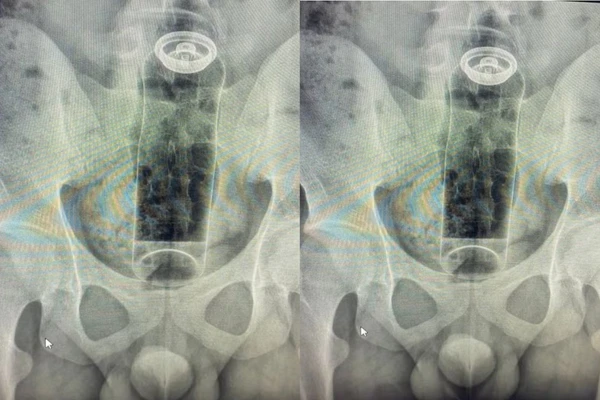

Um rapaz de 19 anos precisou de internação hospitalar depois que uma embalagem de desodorante, inserida no ânus durante uma brincadeira íntima, foi sugada para o interior do reto e não conseguiu ser retirada em casa. O atendimento foi realizado pelo cirurgião coloproctologista Daniel Brosco, que decidiu compartilhar o ocorrido nas redes sociais para alertar sobre os perigos envolvidos.

O paciente relatou ao médico que utilizou o objeto como parte de uma fantasia sexual, mas a embalagem subiu rapidamente devido aos movimentos naturais do intestino, ficando alojada de forma inacessível. Foi necessária intervenção cirúrgica para remoção segura.

Brosco explicou o mecanismo fisiológico por trás desses acidentes: as contrações peristálticas do intestino, responsáveis por movimentar o conteúdo intestinal, combinadas com o efeito de sucção que o reto pode criar, fazem com que objetos soltos sejam puxados para cima em questão de segundos, tornando a extração manual impossível na maioria das vezes.